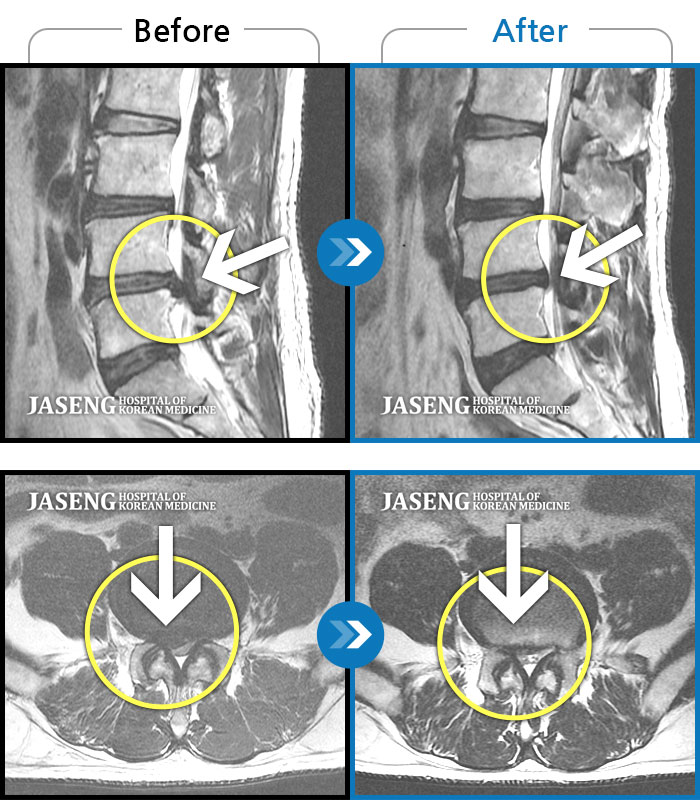

Before

After

환자에게 사전 동의를 받아 동일 조건에서 촬영되었습니다.

개인에 따라 치료 후 부작용이 발생할 수 있으니 의료진과 상담 후 치료를 진행하시기 바랍니다.

허리 통증과 좌측 다리 통증

하요추부 통증, 자가보행이 어렵고 좌측 대퇴부 견인통